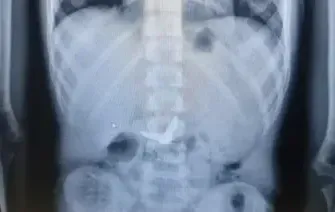

לפי בית החולים, הילד, י', הגיע לחדר המיון בשעות הלילה המאוחרות כשהוא מלווה בהוריו, לאחר שסיפר כי בלע בטעות את המספריים. בצילום רנטגן שבוצע מיד עם קבלתו, התברר כי הלהבים נצפו כשהם פתוחים - בתוך הקיבה. בשל הסיכון המיידי לחתכים ופציעות פנימיות, זומנו במהירות לצוות הרפואי מומחים מתחומי כירורגיית ילדים, גסטרואנטרולוגיה, ואנדוסקופיה, בהם ד"ר אורן לדר, המתמחה בפרוצדורות אנדוסקופיות בילדים.

"מיד לאחר שהילד הורדם כהכנה לניתוח חירום, ערכנו צילום נוסף כדי לאתר את המיקום המדויק של המספריים", מסבירה ד"ר אסתר אורלינסקי-מאייר, רופאה בכירה בגסטרואנטרולוגיה ילדים. "להפתעתנו, ראינו שהמספריים נסגרו מעצמם - דבר שהפחית באופן משמעותי את הסיכון לקרעים ופגיעות פנימיות. הם כבר לא היו בקיבה, אלא התקדמו לעומק המעי הדק".